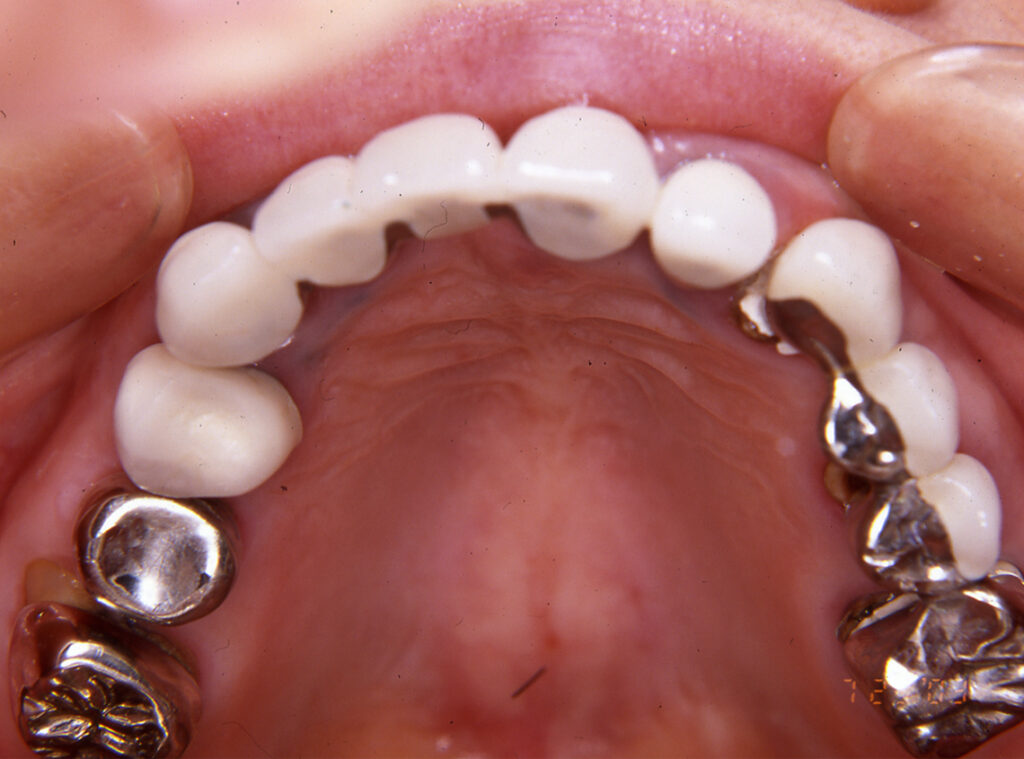

フルマウス治療17年間経過症例

患 者 : S.K様 女性

主 訴 : 補綴物破損、義歯不適による咀嚼障害のためインプラント治療希望

初診日 : 2003年07月11日

1.初診時(2003年)

2.ブリッジ除去後治療用仮歯のブリッジ装着